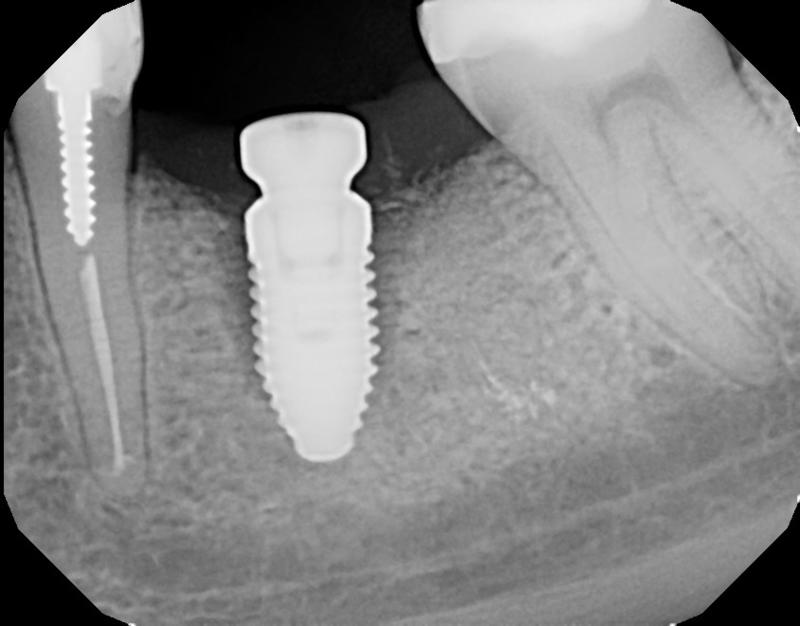

How to handle the infection?

Learn the steps to not only remove the infected implant, but also rebuild the site